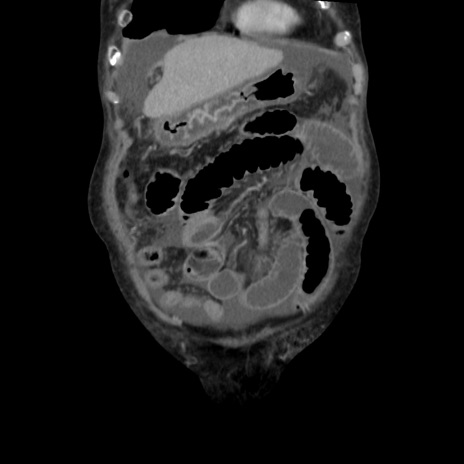

症例31(冠状断像)

【症例】80歳代 女性

【主訴】腹部膨満感

【現病歴】他院にて肝硬変にてフォロー中。1週間前から便秘、腹部膨満感、臍部腫瘤あり受診となる。

【既往歴】肝硬変

【身体所見】腹部膨隆あり、皮膚変化なし、疼痛なし。

【データ】WBC 4600、CRP 0.25